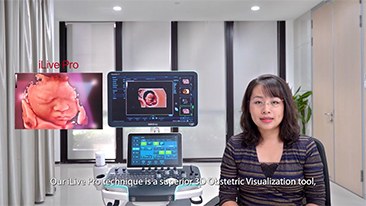

Com a plataforma ZST+ avan?ada, as solu??es inteligentes full-stack do Nuewa s?o projetadas especialmente para melhorar a saû¤de da mulher durante toda a gesta??o, desde o perûÙodo que antecede ao que procede û gravidez e û recupera??o pû°s-parto, a fim de oferecer diagnû°sticos abrangentes e eficientes para atender aos desafios clûÙnicos cada vez mais exigentes.